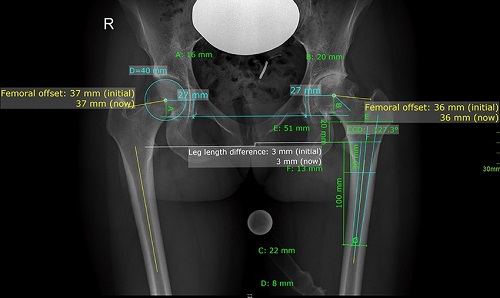

3. Xác định độ bù chiều dài của chân trước và sau phẫu thuật và hiển thị trực quan bằng hình ảnh.

MediCAD 2D Hip tạo điều kiện thuận lợi cho việc trao đổi phục hình bằng cách hiển thị các mô cấy đã được cấy ghép.

5. Xác định chênh lệch offset của xương đùi hai bên

Các thuật toán đo lường mới với sự hỗ trợ của máy tính đã được thiết lập để hỗ trợ bác sĩ phẫu thuật trong quá trình thay toàn bộ khớp trong mổ. Bác sĩ có thể đánh giá chiều dài chân và độ lệch được đo bằng hệ thống định vị đáng tin cậy trong quá trình tạo hình khớp háng .

Ước tính đền bù xương đùi. Độ di lệch xương đùi được định nghĩa là khoảng cách giữa trục dọc ở giữa của xương đùi đến tâm xoay của khớp háng.